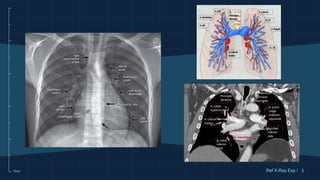

REPASO ANATOMICO DE LA VASCULATURA

PULMONAR

PATRÓN VASCULAR NORMAL

La vasculatura pulmonar

sigue una distribución

arbiriforme.

Se debe ver del pulmón 1-

2 cm por dentro de la

pleura

Ambos hilios deben ser

simetricos (el derecho más

caudal)